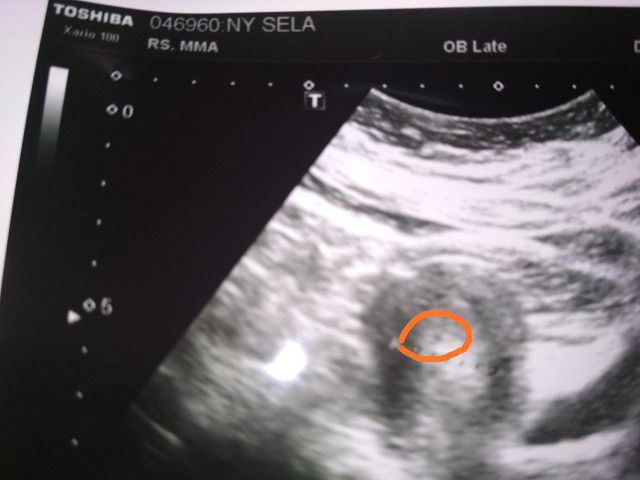

Puji Tuhan bun td abis cek ke dokter specialis kandungan dan hasilnya positif dan udh ada penebalan janin dan kantong janin na udh keliatan cumen msh kecil... Mohon doa na ya bun smoga calon ibu dan calon baby na sehat dan kuat di kehamilan kedua ini aminnn...